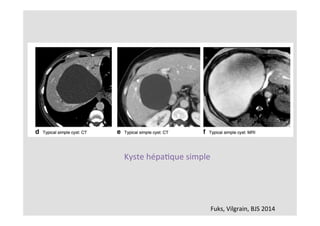

Fuks,	Vilgrain,	BJS	2014

Kyste	hépaKque	simple